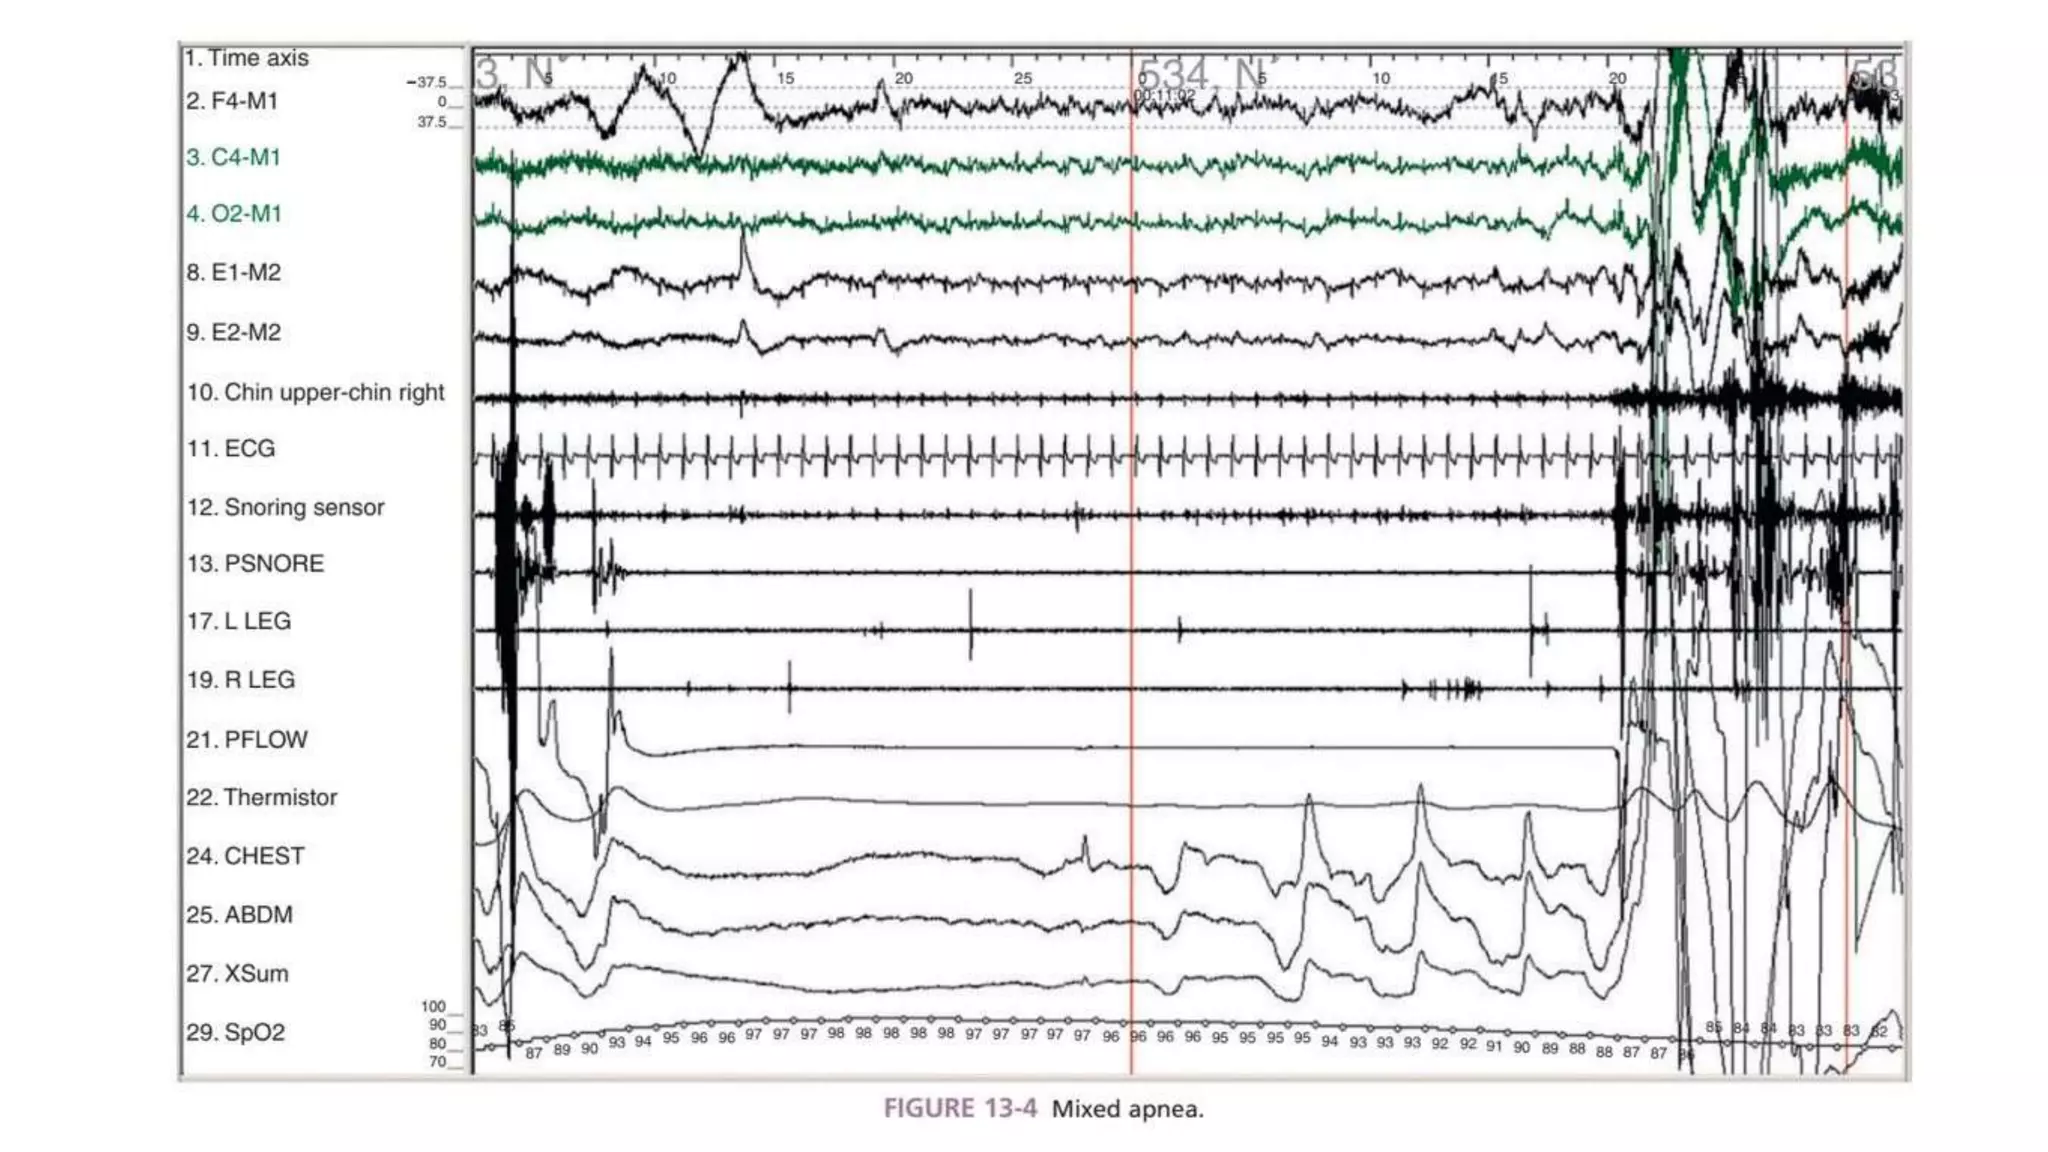

Polysomnography is a comprehensive sleep study that involves monitoring biophysiological changes during sleep including brain waves, eye movements, muscle activity, heart rate, respiration, and oxygen levels. It is used to diagnose various sleep disorders like sleep apnea, insomnia, narcolepsy, and parasomnias. A polysomnography study involves setting up various sensors on the patient's head and body according to international standards and analyzing the recorded data to identify sleep stages and respiratory events during sleep. Polysomnography is considered the gold standard for diagnosing sleep disordered breathing like obstructive sleep apnea.